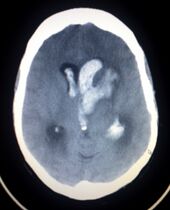

CT scan slice of the brain showing a right-hemispheric ischemic stroke (left side of image).

السكتة القصورية Ischemic stroke

هي سكتة نتيجة قصور في الدورة الدموية الدماغية وتمثل 80% من الحالات. وفيها يقل الدم الواصل لجزء ما في المخ مما يؤدي الى موت هذا الجزي وهذا يكون لسبب من الأسباب الآتية :